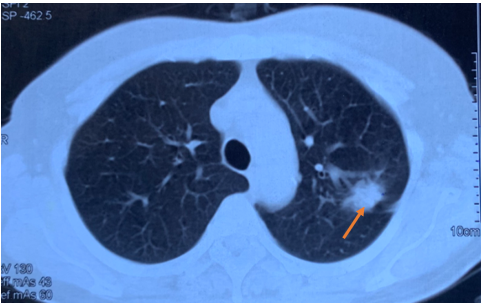

Hình ảnh cắt lớp vi tính lồng ngực tháng 6 năm 2017 khối u thùy trên phổi phải xâm lấn rãnh liên thùy (mũi tên).

Kết quả chụp cắt lớp vi tính (CT) lồng ngực cho thấy khối u thùy trên phổi trái kích thước 20x15mm, bờ tua gai, xâm lấn rãnh liên thùy, kèm theo nhiều nốt mờ rải rác hai phổi, kích thước 5-10mm, phù hợp với tổn thương thứ phát, cùng hạch rốn phổi trái kích thước 10mm.